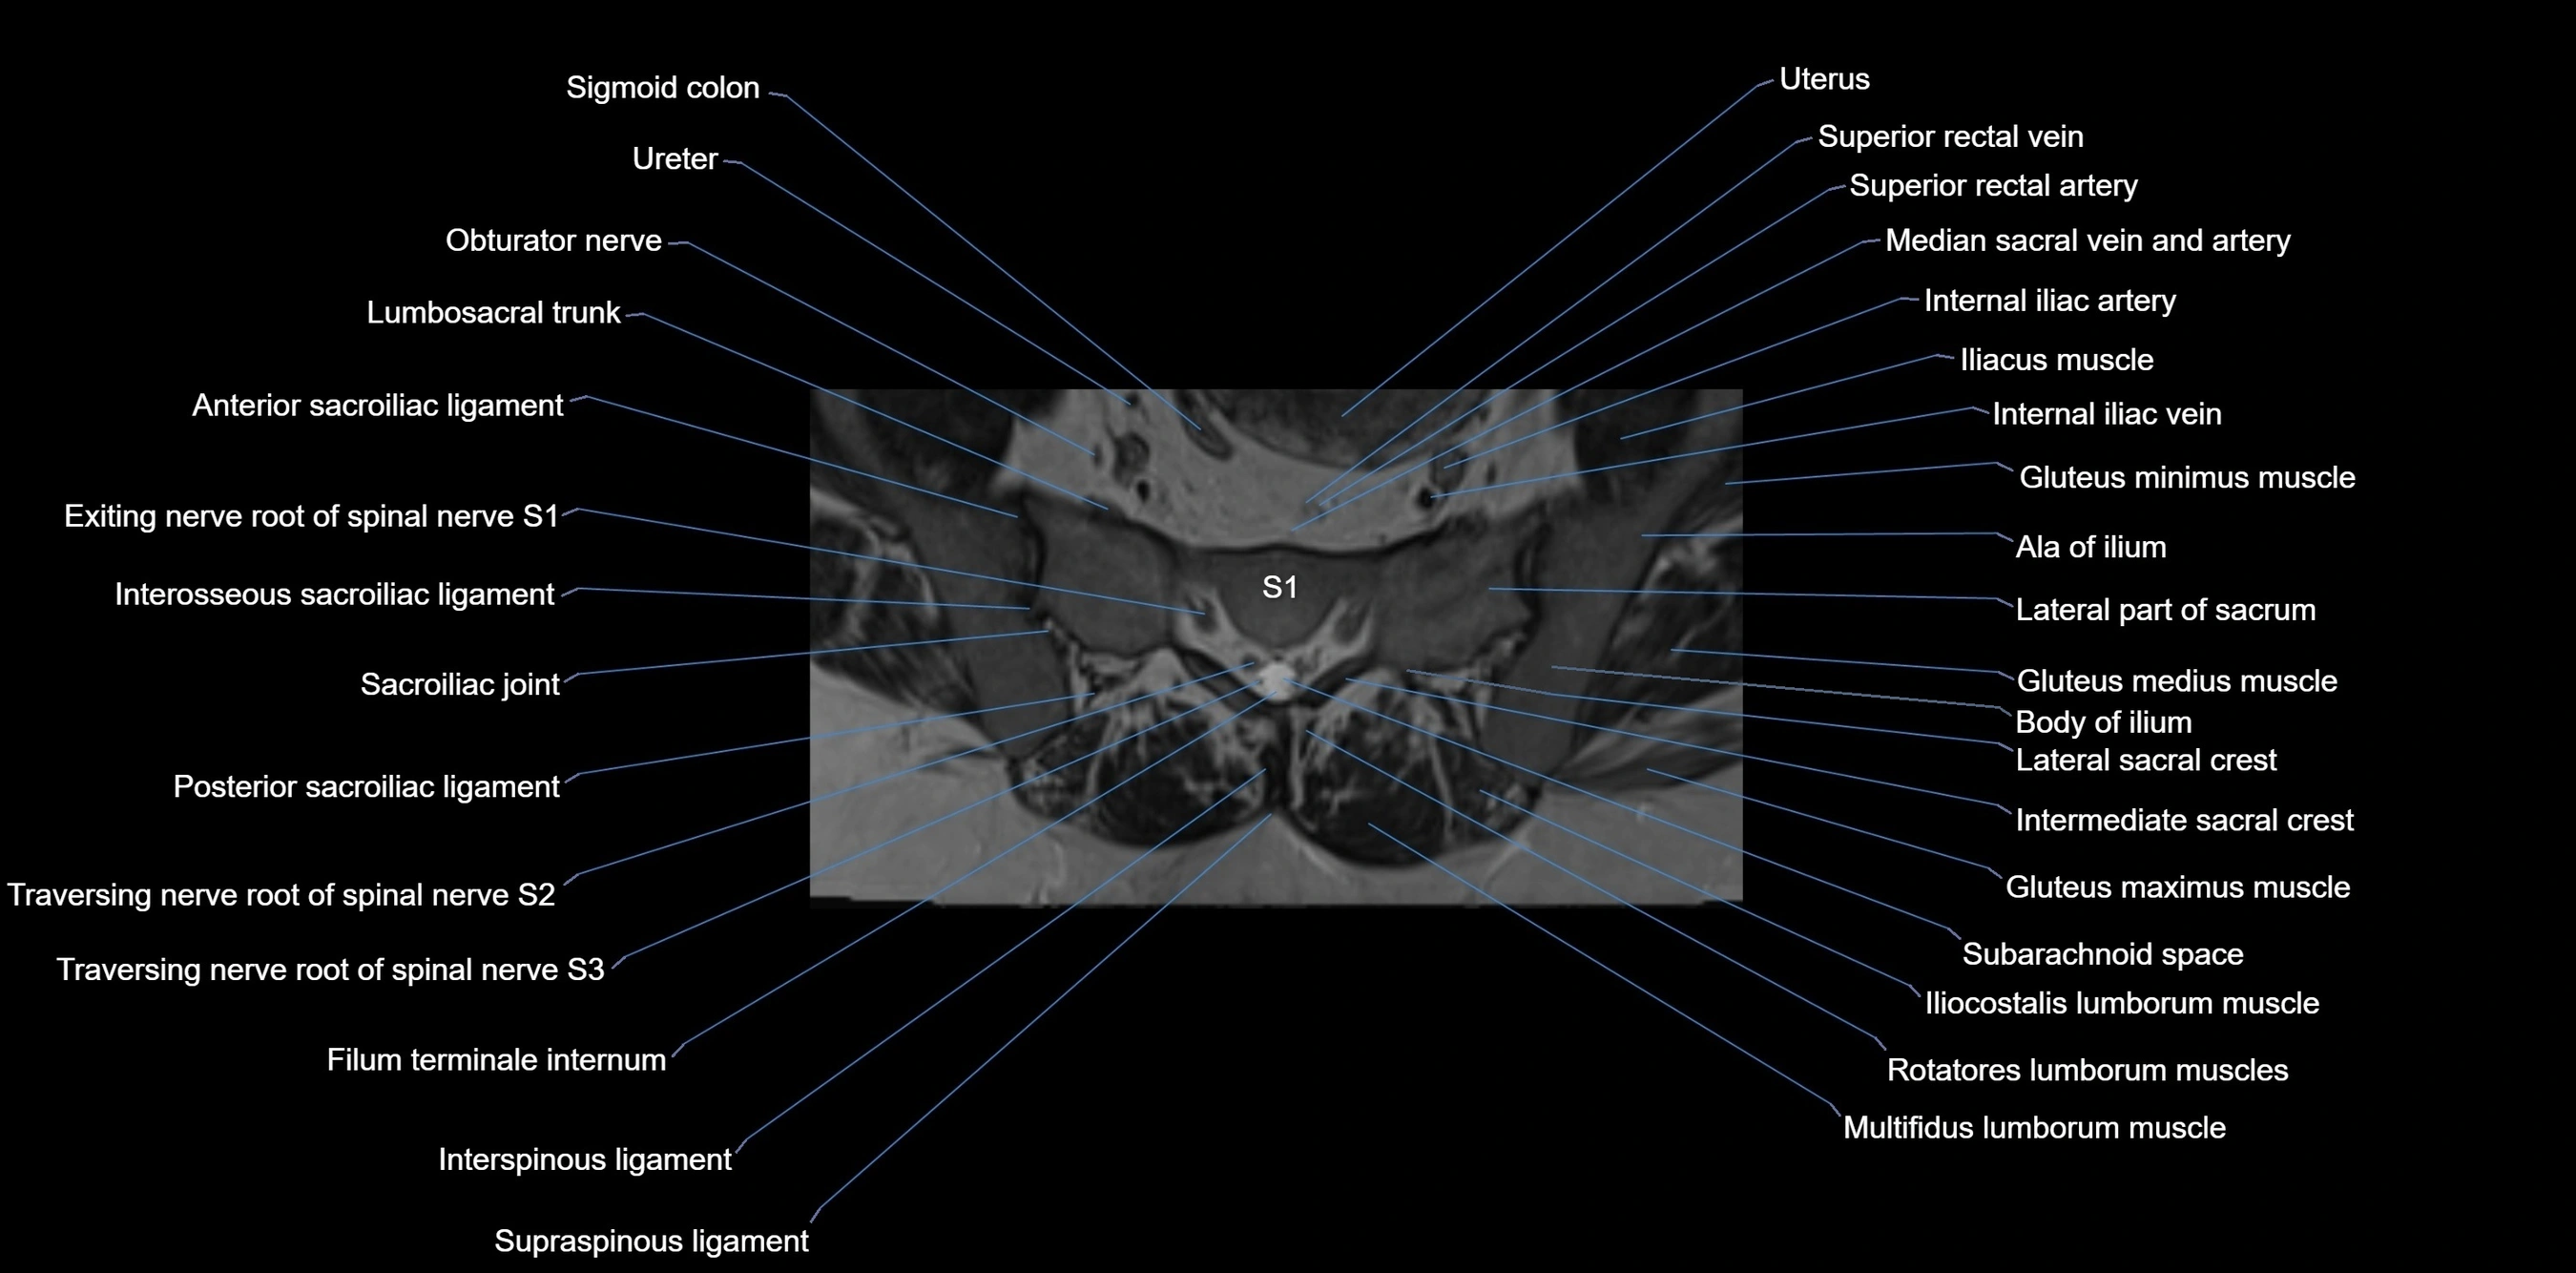

MRI image

image